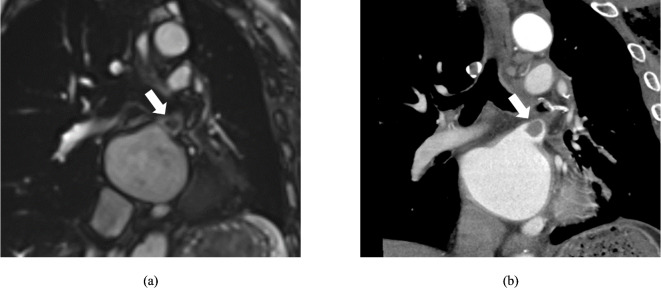

The purpose of this study is to evaluate left atrial function using cine-magnetic resonance imaging (cine-MRI) in patients with pulmonary vein stump thrombus (PVST) after left upper lobectomy (LUL). The study population comprised 91 patients (30 with PVST and 61 without PVST) who underwent LUL for pulmonary lesions and evaluation by cine-MRI. Left atrial functional parameters were evaluated and compared between patients with and without the development of PVST after LUL using the Mann-Whitney U test. The diagnostic capabilities of these parameters for predicting PVST development were assessed using receiver-operating characteristic (ROC) curve analysis. Clinical and left atrial functional parameters were analyzed by multivariate logistic regression models to determine predictors of PVST. Left atrial end-systolic volume (LAESV), left atrial end-diastolic volume (LAEDV), LAESV index (LAESVI), and LAEDV index (LAEDVI) were significantly greater in patients who developed PVST than in those without PVST (p = 0.009, < 0.001, 0.004, and < 0.001, respectively). Left atrial ejection fraction (LAEF) was significantly lower in patients who developed PVST than in those without PVST (p < 0.001). The area under the ROC curve for predicting PVST was 0.668, 0.769, 0.688, 0.792, and 0.803 for LAESV, LAEDV, LAESVI, LAEDVI, and LAEF, respectively. In the multivariate logistic regression analysis, only LAEF was identified as an independent predictor of PVST (OR 0.896; 95% CI 0.846-0.950). In conclusion, left atrial enlargement and left atrial dysfunction were associated with the development of PVST after LUL.